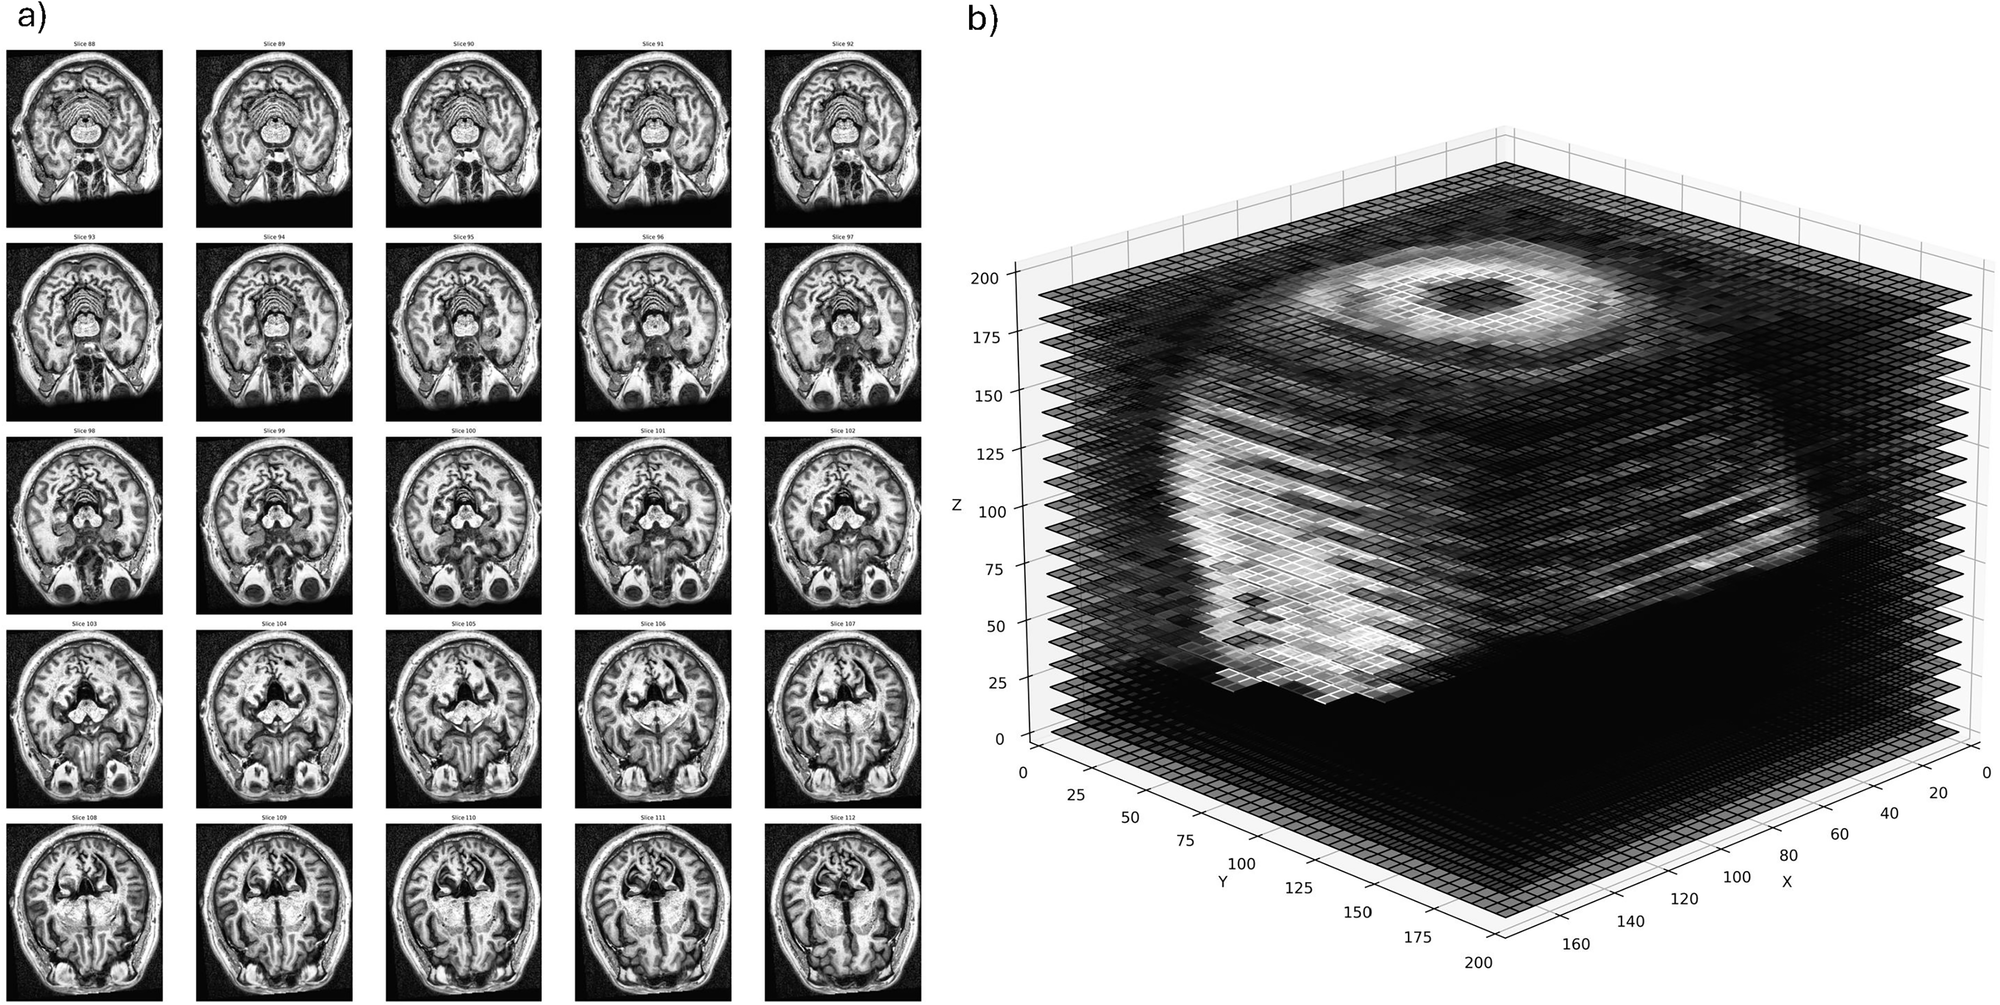

Fig. 1: MRI preprocessing approaches for 2D and 3D analysis.

a Example of single slices centered on the midbrain used individually to classify between PD and HC in the two-dimensional analyses. b Entire volumetric MRI scan used in the three-dimensional analyses. Gaps are inserted at regular intervals to help visualize the inner structure, but are not implemented in the analyses.